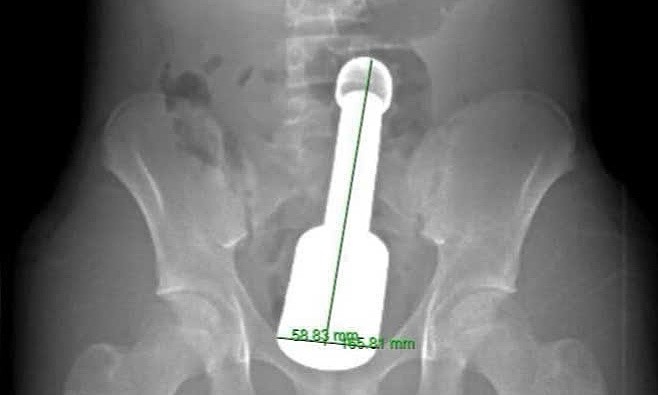

Hình ảnh chụp chiếu phát hiện dị vật trong trực tràng. Ảnh: Bệnh viện cung cấp